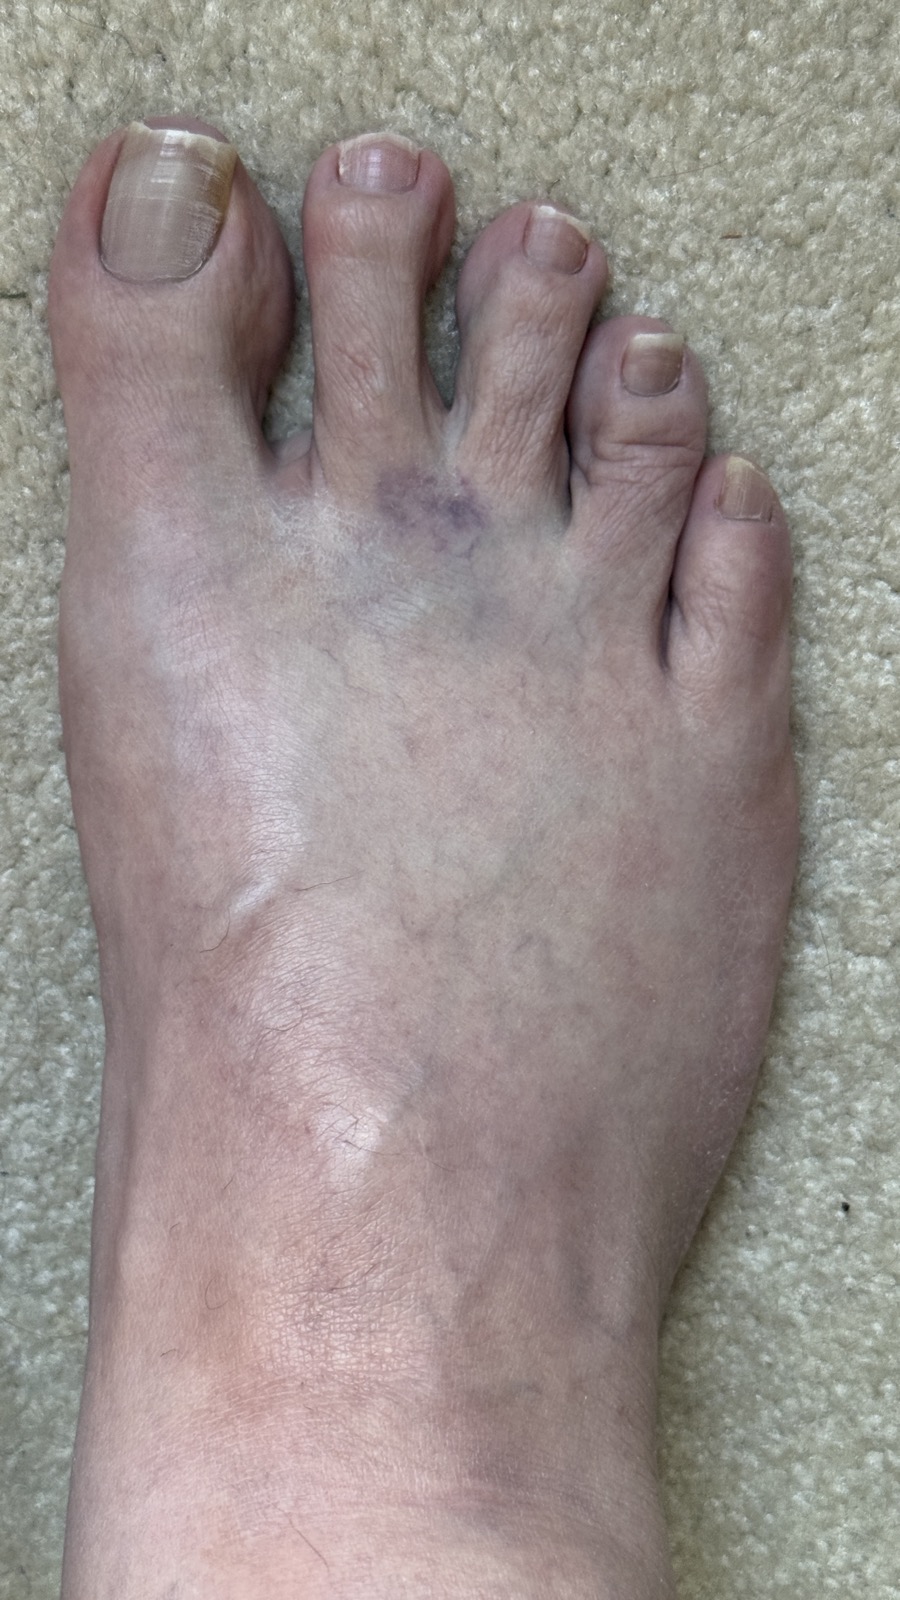

February 19: Got a steroid injection from my podiatrist in my right foot to help with the previously mentioned Morton’s Neuroma. This was the second or third injection in this foot over the span of probably 18-24 months. The injection hurt more than the previous injections, but needles hurt, so I didn’t think anything of it.

March 4: At my follow-up with the podiatrist I told him that my foot was still bruised he said something to the effect of, Sorry for the hematoma (bruise) – may have nicked a vein. It did not hurt, but it looked ugly, and since it seemed like a minor thing none of us were concerned. He couldn’t really do anything for my foot with my back interfering and so now I was at the point with competing doctors who weren’t talking with each other due to being affiliated with different hospitals.

March 13: While taking a shower I noticed that one leg was very swollen. In my daily vitals log I wrote, Right leg swollen, WTF?  It did not hurt, it was not red, and it was not hot, but I had been dealing back pain with all sorts of right leg symptoms, so this just seemed like another one. Why do I have all these pics? Because I am an obsessive data hoarder who was an engineer and consultant for decades. Any time anything unusual happens to me (or around me) I take pictures because they help me determine a root cause later, if need be.

March 14: I took this picture of my swollen foot because I thought it was interesting that I still had the bruise from the injection which I had received just shy of a month prior (February 19). Note the swelling in my foot compared to the previous picture. That is not a happy foot.